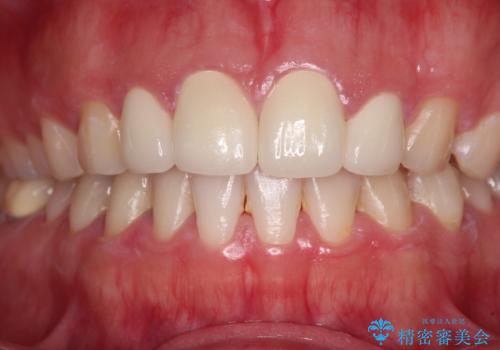

- 前歯の矮小歯と捻れや変色を気にして来院された患者様です。

結婚式が近いということもあり、前歯4本をオールセラミッククラウンにて補綴治療することとしました。

前歯の捻れは、オールセラミッククラウンよりも矯正治療による改善の方が、歯を削らなくて済むためお勧めとなります。

しかし、矮小歯の改善はオールセラミッククラウンでの補綴治療が必要であり、幅径のバランスを取る必要があるため、4前歯の補綴治療を選択しました。